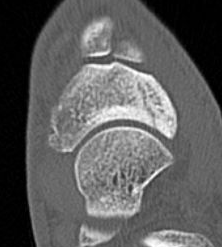

CT

Displaced navicular stress fracture